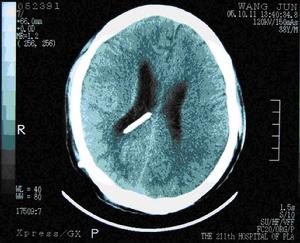

頭顱1.影像學檢查 頭顱CT 檢查是正常顱壓腦積水檢查重要手段,它可確定腦室擴大和皮質萎縮的程度及引起腦積水的病因,同時,也是觀察術後分流效果及併發症的手段。典型的CT 掃描表現為腦室擴大而皮質萎縮不明顯。MRI 影像可從矢、冠、水平全方位觀察較小的顱內病變並優於CT,同時通過MRI 可觀察腦脊液的動力學變化,對腦積水進行評價。腦室周圍T1 加權像低信號改變可表明腦積水呈進展趨勢。

(4)頭顱CT 掃描:腦溝變淺,腦回縮小,蛛網膜下腔不寬,而腦室擴大明顯和腦室周圍水腫嚴重者分流後效果明顯。